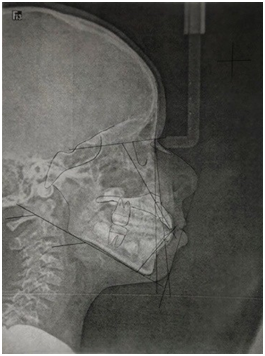

A sample of 24 lateral skull radiographs obtained by the Kodak 8000C Digital Panoramic and Cephalometric System from patients of the Universidad Latina de Costa Rica was used. These were subjected to Steiner and Ricketts cephalometric tracing manually on a negatoscope and with Grafix Cephalometric Tracing acetate, using a 0.5mm lead pencil marking only the necessary anatomical points (Figure 1). Subsequently, the same radiographs were subjected to the Steiner and Ricketts cephalometric tracing in a computerized manner, using Planmeca Romexis® 6.0.1.812 software (Figure 2).